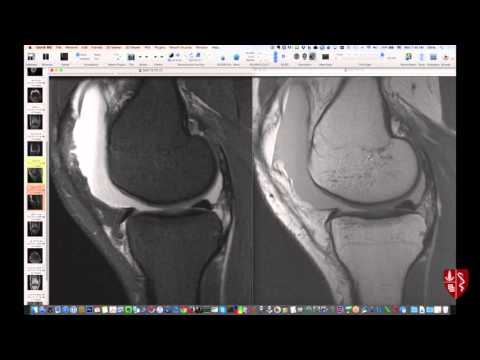

Систематическая интерпретация МРТ коленного сустава: как я это делаю

Эффективный обзор МРТ коленного сустава. Больше случаев можно найти в видео части II и на сайте (используйте Chrome или Firefox). От заведующего отделением радиологии опорно-двигательного аппарата Стэнфордского университета.